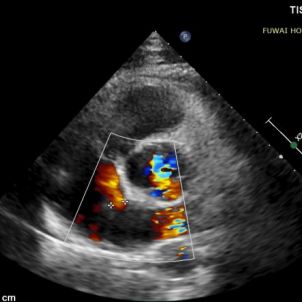

The procedure was guided by TTE following the PAN procedure developed at Fuwai Hospital. This radiation-free, real-time imaging technique offers high-resolution anatomical visualization, ensuring accurate device placement and minimizing complications—particularly valuable in young, reproductive-age patients.

1-day postoperative TTE revealed that the occluder is in good shape without residual shunt (see last figure).